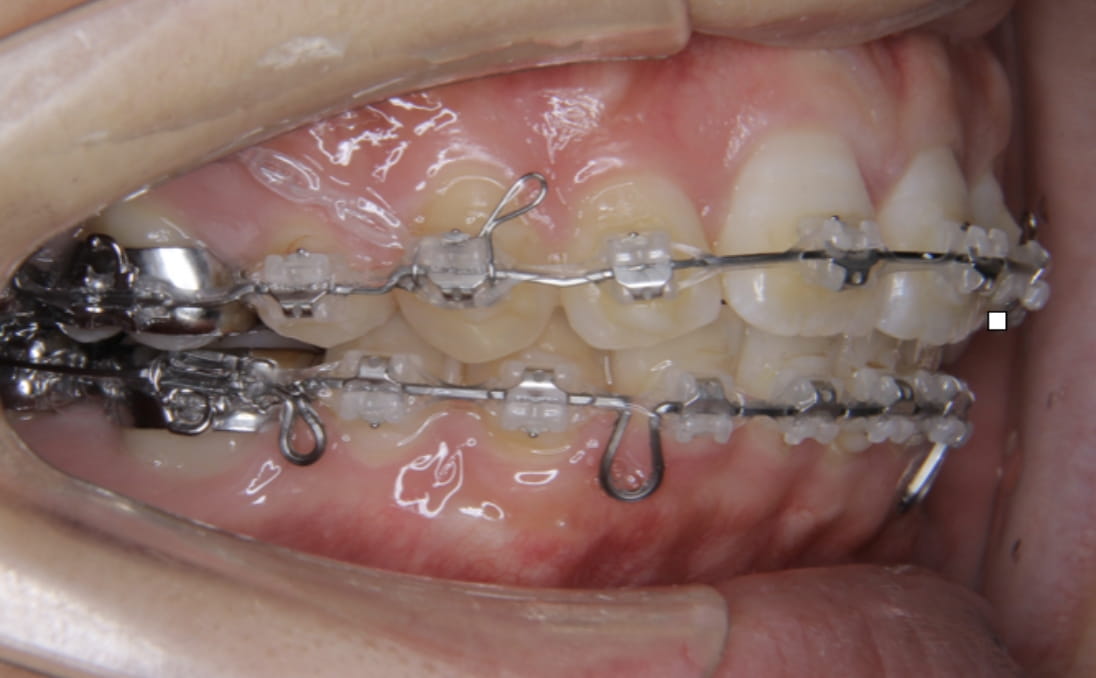

《上下顎前突》

症例

主訴 口ゴボが気になる

治療装置 ハーフリンガル矯正(上顎裏側・下顎表側)

抜歯 抜歯あり

診断名 上下顎前突(口ゴボ)

副作用 歯肉退縮・歯根吸収・歯髄・壊死・癒着による予期せぬ歯の動き

上下顎ともに裏側で装置を完全に隠しながら、アンカースクリューで前歯をしっかり後退。見た目と仕上がりを両立した症例。

治療前

治療中①

治療中②

治療中③

治療後

顔貌